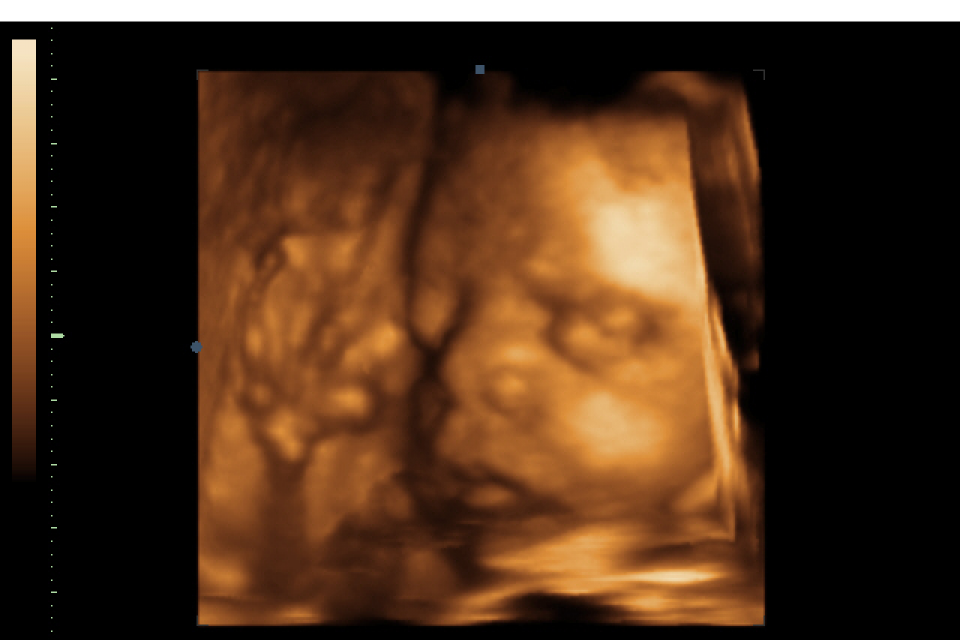

ECOGRAFIA OSTETRICA TRI-QUADRIMENSIONALE

Per la paziente è come una normale ecografia tuttavia raccoglie informazioni che con l'ausilio di un algoritmo contenuto dentro all'ecografo ricostruisce l'immagine del feto in tridimensionale...